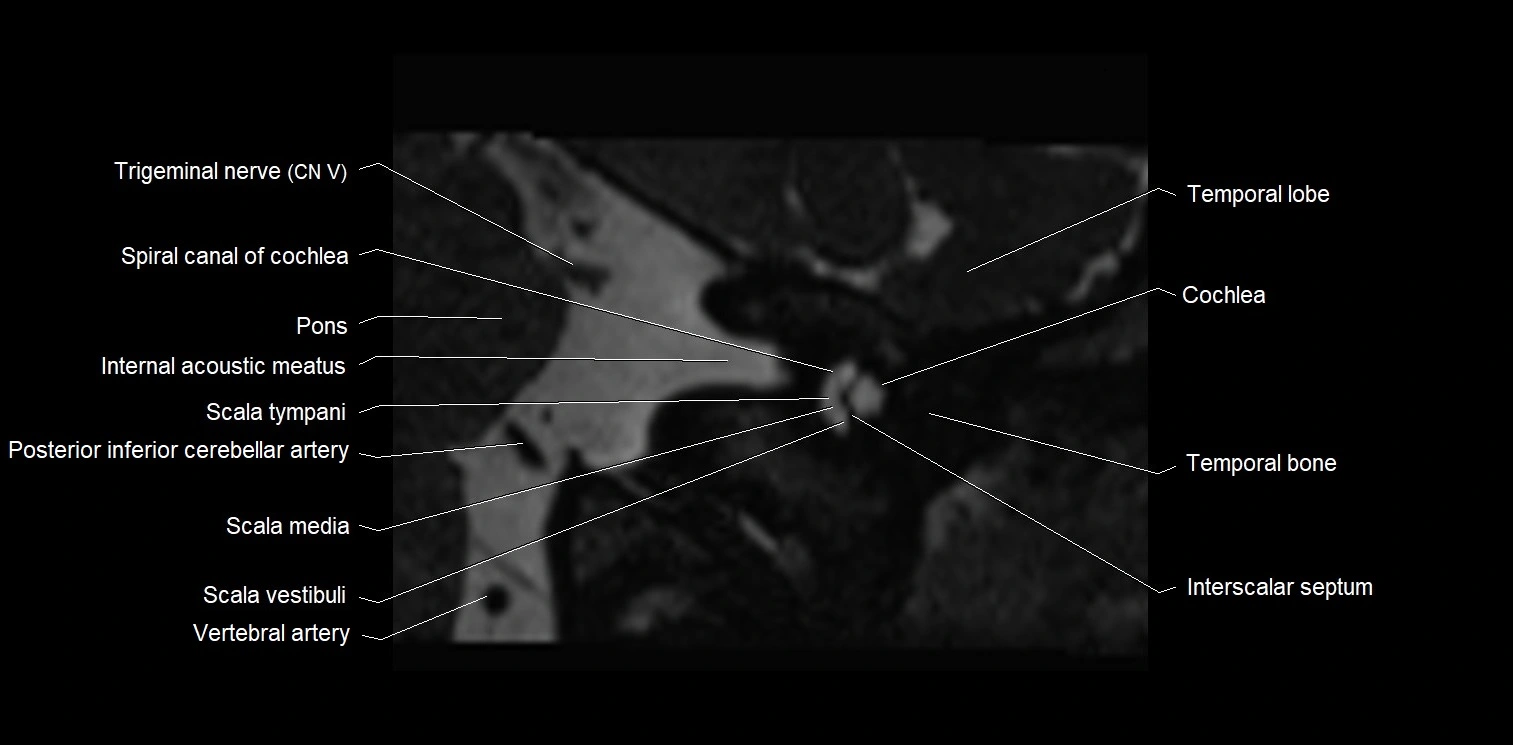

MRI Appearance

• The abducens nerve is a small, thin, linear structure

• Best visualized on high-resolution T2-weighted 3D MRI sequences (e.g., FIESTA or CISS)

• Seen as a hypointense (dark) line running from the brainstem at the pontomedullary junction, traversing the prepontine cistern, and entering Dorello’s canal under the petrosphenoidal ligament, then into the cavernous sinus, and finally the orbit

• May be challenging to visualize in standard MRI due to its small size

• Pathology may be inferred by absence, displacement, or enhancement of the nerve